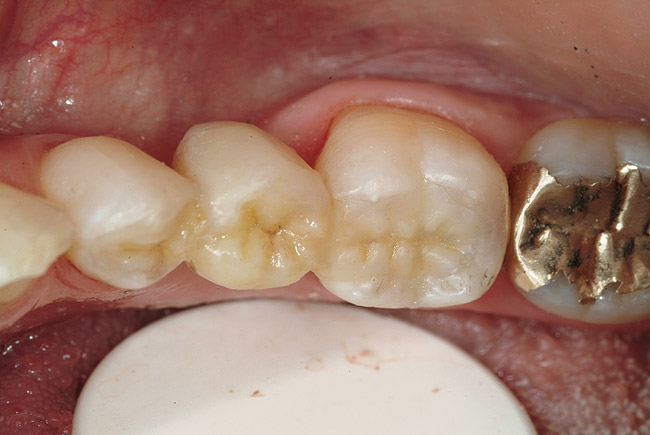

In vitro studies have demonstrated that the use of unidirectional glass-fiber reinforcement in the connector areas of FPDs contributes to significant composite reinforcement.29,36-38,66-68 Similar findings have been reported with a leno-weave UHMWPE and triaxial weave UHMWPE fiber.20,33,36 Fiber-reinforcing materials used by a dental laboratory are either resin pre-impregnated glass fibers, pre-polymerized composite resin surrounding glass fibers, biaxial braid UHMWPE, leno-weave UHMWPE, or a triaxial weave UHMWPE (Table 3). Typically, the preparation designs for the abutment teeth are inlay or onlay preparations (Figure 6A, Figure 6B, Figure 6C, Figure 6D). They are highly successful and can provide the patient with clinical service for more than 5 to 10 years.69 These restorations must be cemented using an adhesive resin technique with resin cements. Both etch-and-rinse adhesives with a self-cure or dual-cure composite resin cement or with a self-adhesive resin cement are indicated for cementing these restorations (Figure 7).36-38,70 Also, fiber-reinforcing materials are being used by dental laboratories in the fabrication of provisional restorations to reinforce and strengthen acrylic and composite-resin provisional materials.15,40,71